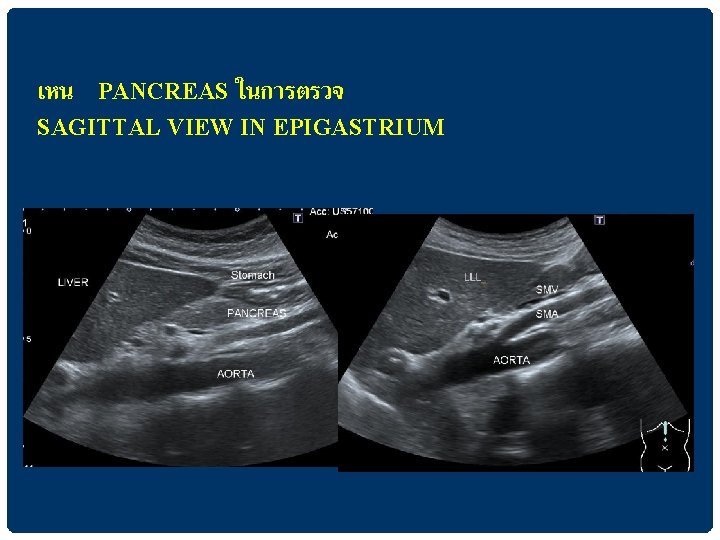

เหน PANCREAS ในการตรวจ SAGITTAL VIEW IN EPIGASTRIUM